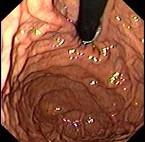

问题 女,28岁,反复上腹痛4年,早饱嗳气,无黑便史,便秘腹泻交替,胃镜检查如图,近来B超肝胆脾胰未见异常。最可能的诊断 ( )

选项 A、十二指肠球炎 B、弥漫性胃癌 C、慢性胰腺炎, D、消化性溃疡 E、功能性消化不良,

答案 E